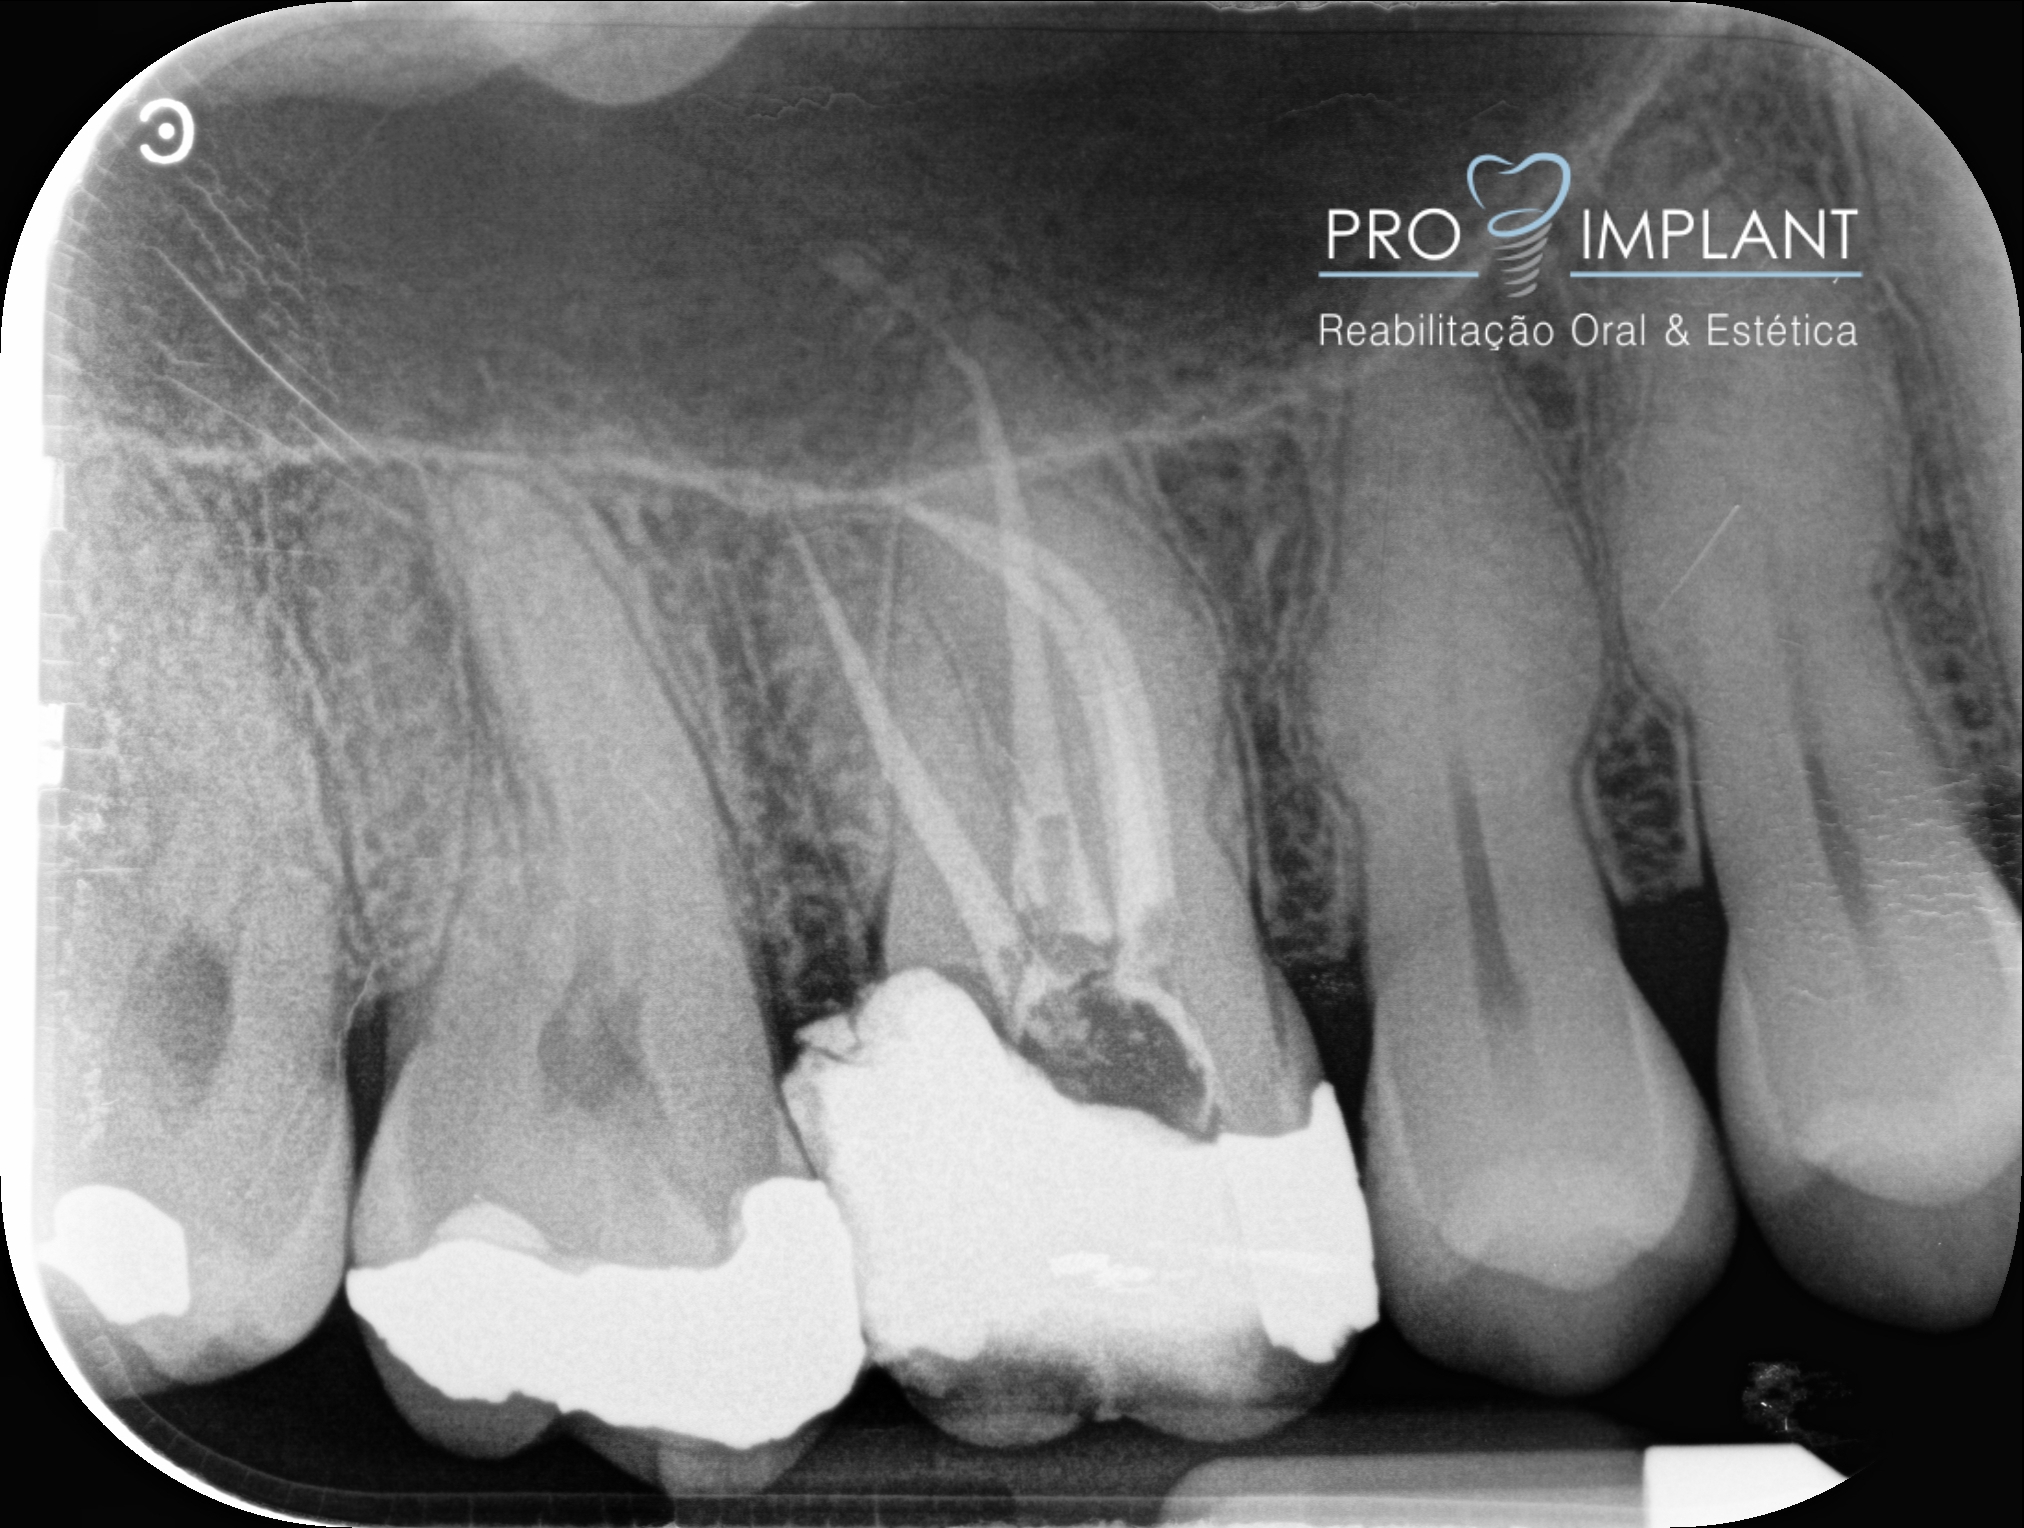

FOTOS

Endodontia